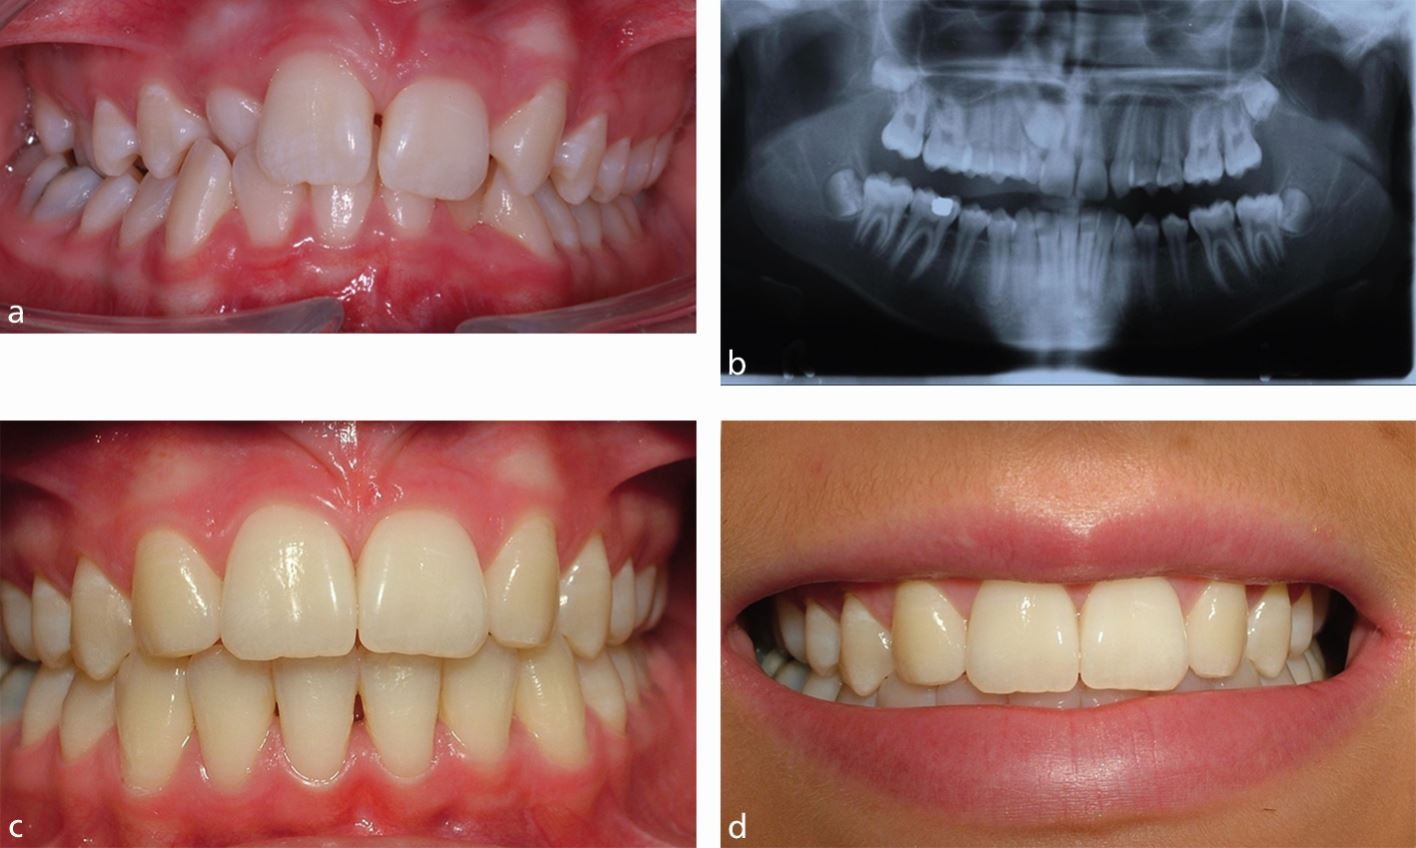

The decision to pursue restorative dentistry, such as implants, bridges, or dentures, is therefore as much a psychological investment as a physical one. Successful oral rehabilitation is frequently reported by patients not merely in terms of renewed chewing capacity, but more significantly, as a restoration of confidence and a reclaimed ability to smile freely and communicate openly without self-consciousness. The aesthetic outcome serves as a powerful psychological antidote to the earlier feelings of shame and unworthiness. It grants a tangible closure to the period of self-imposed isolation, allowing the individual to reintegrate fully into their social and professional life with a renewed sense of self-acceptance and composure.